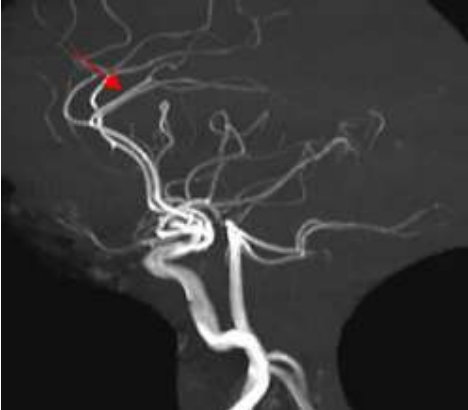

Analise a imagem abaixo.

Assinale a alternativa que apresenta a estrutura vascular apresentada pela seta.